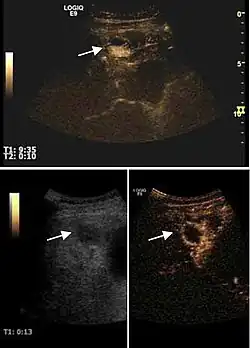

The suggestive appearance of early HCC on 2D ultrasound examination is that of hypoechoic nodule, with distinct pattern, developed on cirrhotic liver. Hypoechoic appearance is characteristic of moderate/poorly differentiated HCC, with low or absent fatty changes. Rarely, HCC may appear isoechoic, consist of a tumor type with a higher degree of differentiation and therefore with slower development. Another common aspect is "bright loop" or "nodule-in-nodule" appearance, hypoechoic nodules in a hyperechoic tumor.

Spectral Doppler characteristics of early HCC overlap those of the dysplastic nodule, as they are represented by the presence of portal venous signal type or arterial type with normal RI (well differentiated HCC) or increased RI (moderately or poorly differentiated HCC). The CFM exploration identifies a chaotic vessels pattern.

On CEUS examination, early HCC has an iso- or hypervascular appearance during the arterial phase followed by wash out during portal venous and late phase. There are studies showing that the wash out process is directly correlated with the size and features of neoplastic circulatory bed. Thus, highly differentiated HCC illustrates the phenomenon of late or even very late "wash out" while poorly differentiated HCC has an accelerated wash out at the end of arterial phase. It is therefore mandatory to analyze all these three phases of CEUS examination for a proper characterization of liver nodules. Tumor wash out at the end of the arterial phase allows the HCC diagnosis with a predictability of 89.5%. Some authors consider that early pronounced contrast enhancement of a nodule within 1–2 cm developed on a cirrhotic liver is sufficient for HCC diagnosis. These results prove that for a correct characterization of the lesions it is necessary to extend the examination time to 5 minutes or even longer.